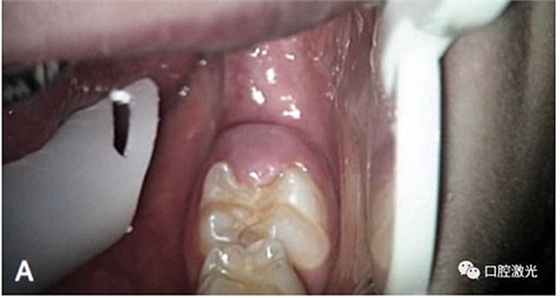

激光盲袋切除術(shù)前